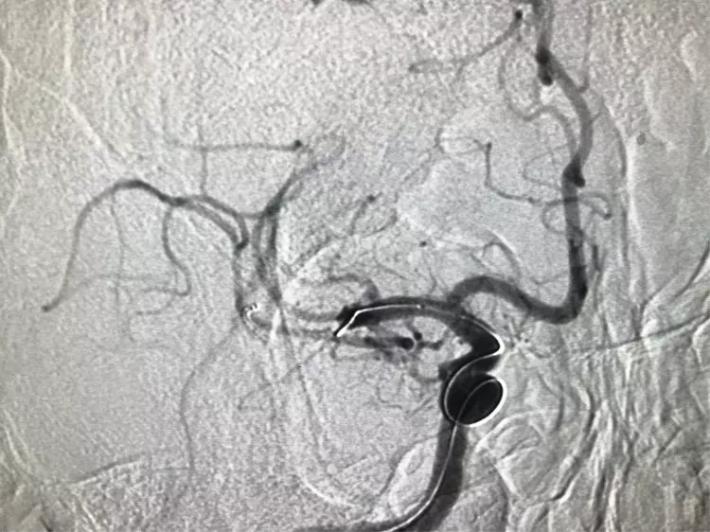

立即桥接取栓,造影显示:左侧颈内动脉闭塞。

右侧颈内动脉向左侧没有代偿。

椎动脉造影显示后交通动脉没有代偿。

微导管进入左侧大脑中动脉远端真腔。

置入支架。

可见大脑中动脉有血流。

取出支架未见血管开通。

再次置入微导管。

置入支架取栓。

见颈内动脉开通,大脑中动脉远端有血栓逃逸。